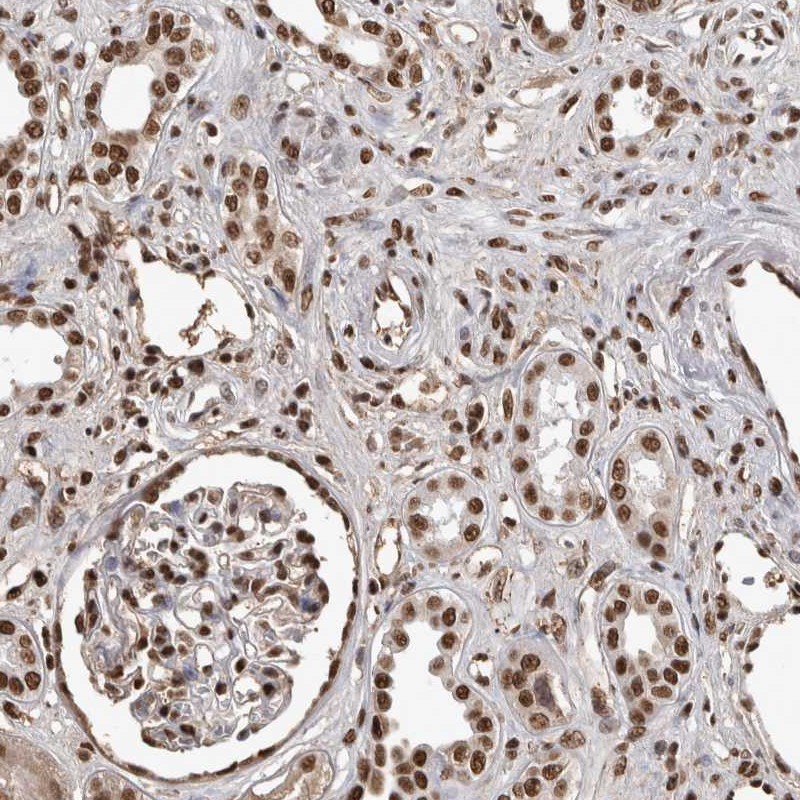

Immunohistochemical staining of human kidney shows strong nuclear positivity in tubular and glomerular cells.